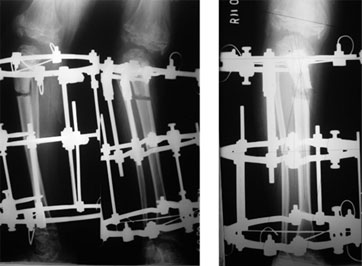

The deformity in the proximal tibia was corrected using the gradual correction using Ilizarov ring fixator and hinges.

The fixator is first applied in a crooked fashion, to mimic the deformity of the bone. With gradual distraction @ 1 mm/day the fixator is adjusted and the bone moves with the fixator creating a gap at the osteotomy site(the bone cut).

The gap shown in the xray is the site of osteotomy & correction of the deformity.

The picture on the right side shows correction achieved in terms of the angle and length. The fuzzy appearance in the bone gap is due to the formation of new bone in the gap. |